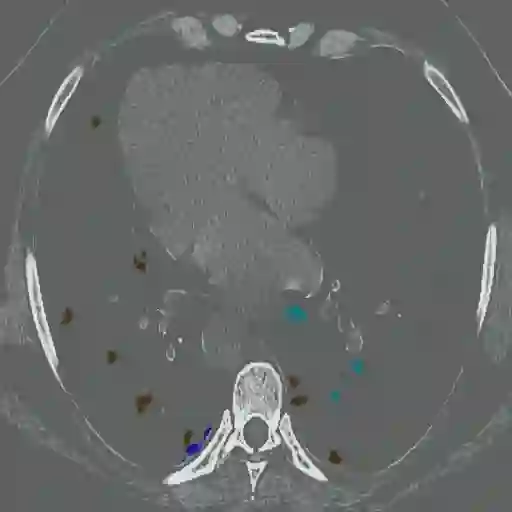

The novel coronavirus disease 2019 (COVID-19) has been spreading rapidly around the world and caused significant impact on the public health and economy. However, there is still lack of studies on effectively quantifying the lung infection caused by COVID-19. As a basic but challenging task of the diagnostic framework, segmentation plays a crucial role in accurate quantification of COVID-19 infection measured by computed tomography (CT) images. To this end, we proposed a novel deep learning algorithm for automated segmentation of multiple COVID-19 infection regions. Specifically, we use the Aggregated Residual Transformations to learn a robust and expressive feature representation and apply the soft attention mechanism to improve the capability of the model to distinguish a variety of symptoms of the COVID-19. With a public CT image dataset, we validate the efficacy of the proposed algorithm in comparison with other competing methods. Experimental results demonstrate the outstanding performance of our algorithm for automated segmentation of COVID-19 Chest CT images. Our study provides a promising deep leaning-based segmentation tool to lay a foundation to quantitative diagnosis of COVID-19 lung infection in CT images.

翻译:2019年新的冠状病毒疾病(COVID-19)在全世界迅速蔓延,对公共卫生和经济产生了重大影响;然而,对于有效量化COVID-19造成的肺感染,仍然缺乏研究;作为诊断框架的一项基本但具有挑战性的任务,分解在通过计算断层摄影(CT)图像测量的COVID-19感染的准确量化方面发挥着关键作用;为此,我们提出了对多个COVID-19感染区域进行自动分解的新型深层次学习算法。具体地说,我们利用综合残余变异学来学习一种稳健和直观的特征表征,并运用软关注机制来提高模型的能力,以区分COVID-19的症状。用公共CT图像数据集,我们验证了拟议的算法与其他相竞方法的功效。实验结果表明,我们自动分解COVID-19 Chest CT 图像的算法表现出色。我们的研究提供了一个充满希望的深度精细分解工具,为CT 图像中COVID-19肺感染的定量诊断奠定了基础。